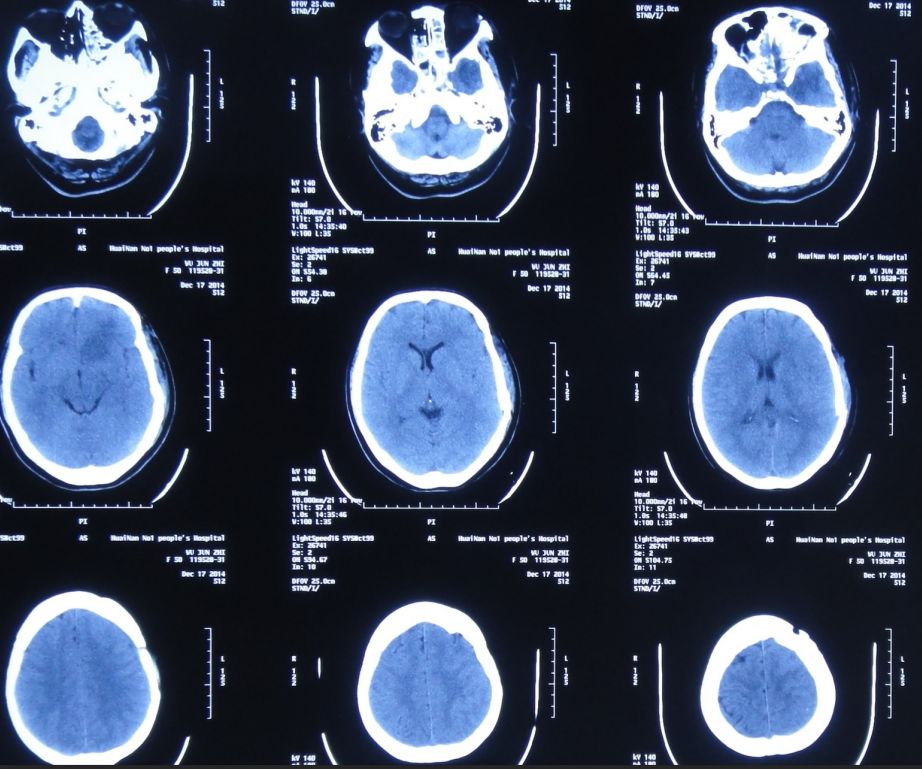

入院后第1天即2015年8月8日,复查头CT头:脑脊液蝶窦瘘征象。脑室扩张,双侧额叶片状密度减低,左侧额叶软化灶形成;脑沟、裂变浅;鞍上池及右侧脑室前角积气(图17)。

![]()

图17:2015年8月8日头CT:脑室扩张,鞍上池及右脑室前角积气